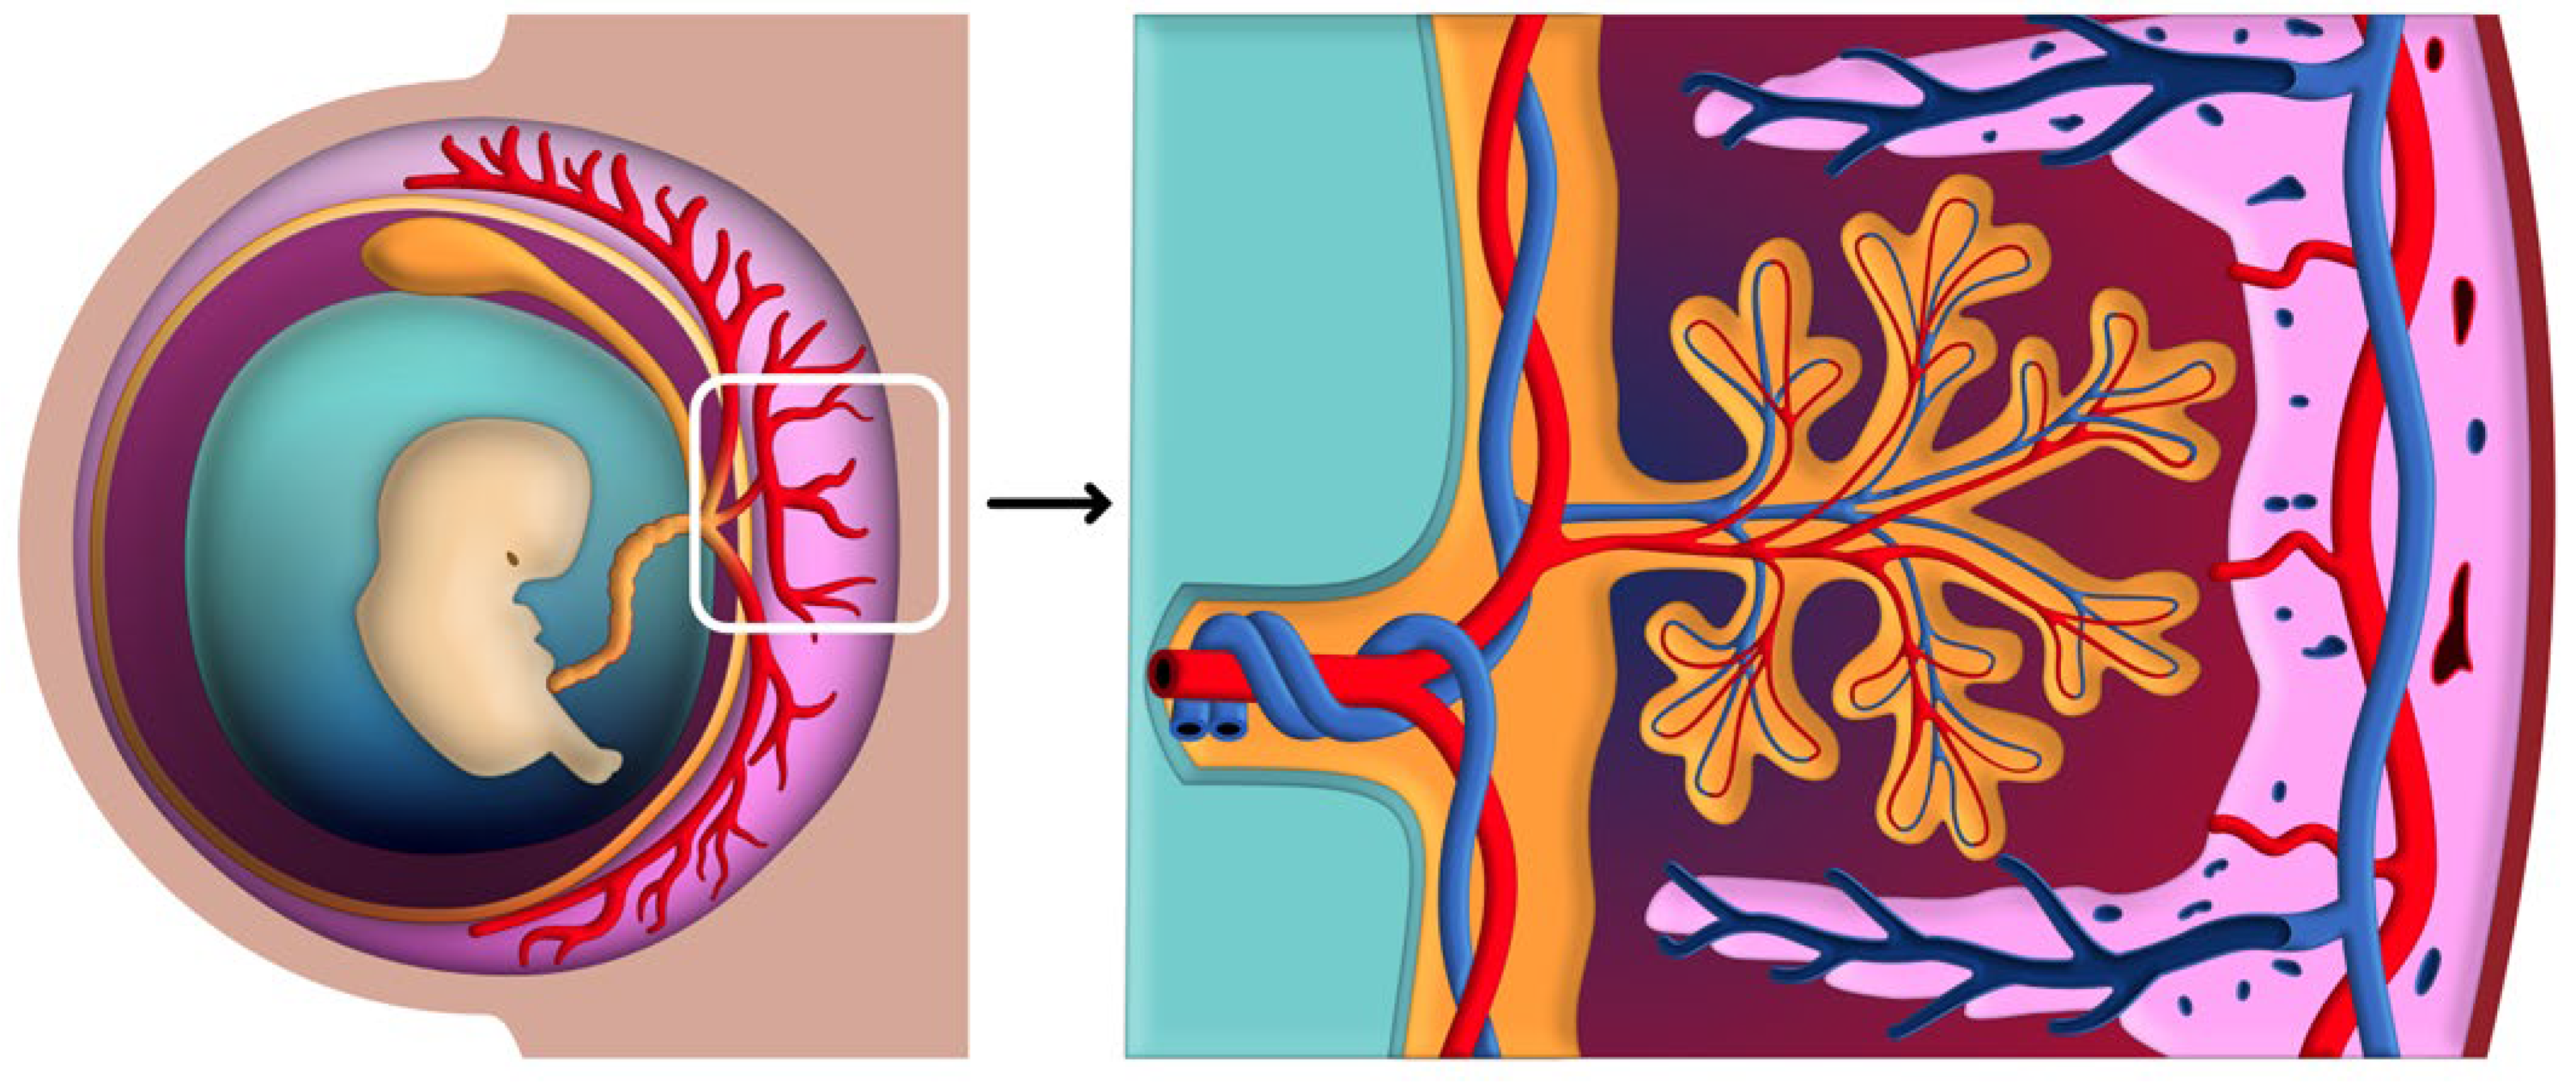

2. The Organogenesis of the Placenta

2.1. Early Placental Development

3. Placental-Uterine Interface and Circulatory Systems

3.1. Structural Components of the Placental-Uterine Interface

3.3. Establishment and Regulation of Uteroplacental Circulation

3.3.2. Intervillous Space and Maternal-Fetal Blood Flow

4.1. Chorionic Plate

4.2. Basal Plate

4.3. Intervillous Space